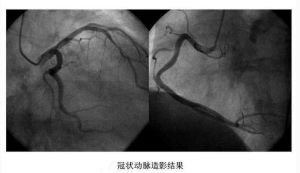

冠脈造影冠狀動脈造影是診斷冠心病的一種有效方法。將導管經大腿股動脈或其它周圍動脈插入,送至升主動脈,然後探尋左或右冠狀動脈口插入,注入造影劑,使冠狀動脈顯影。能較明確地揭示冠狀動脈的解剖畸形及其阻塞性病變的位置、程度與範圍。冠狀動脈造影是目前唯一能直接觀察冠狀動脈形態的論斷方法,醫學界號稱其為“金標準”。冠狀動脈造影術的死亡率約在0.11%-0.14%,心肌梗死率約在0%-0.06%;左冠狀動脈主幹病變患者的心肌梗死與死亡率均約在3.0%。